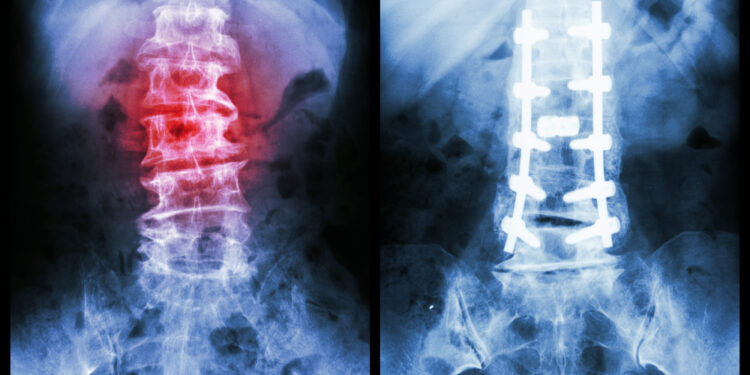

- Rentgenas

Diagnozė nustatoma pagal tai, į kurią pusę lenkiasi stuburas – į kairę (levoskoliozė), ar į dešinę (dektroskoliozė).

- Chirurginis gydymas – kai skoliozė progresuoja ar yra labai pažengusi, gali būti atliekama stuburo operacija (pvz., slankstelių fiksacija, kaulų persodinimas) siekiant atstatyti stuburo ašį.